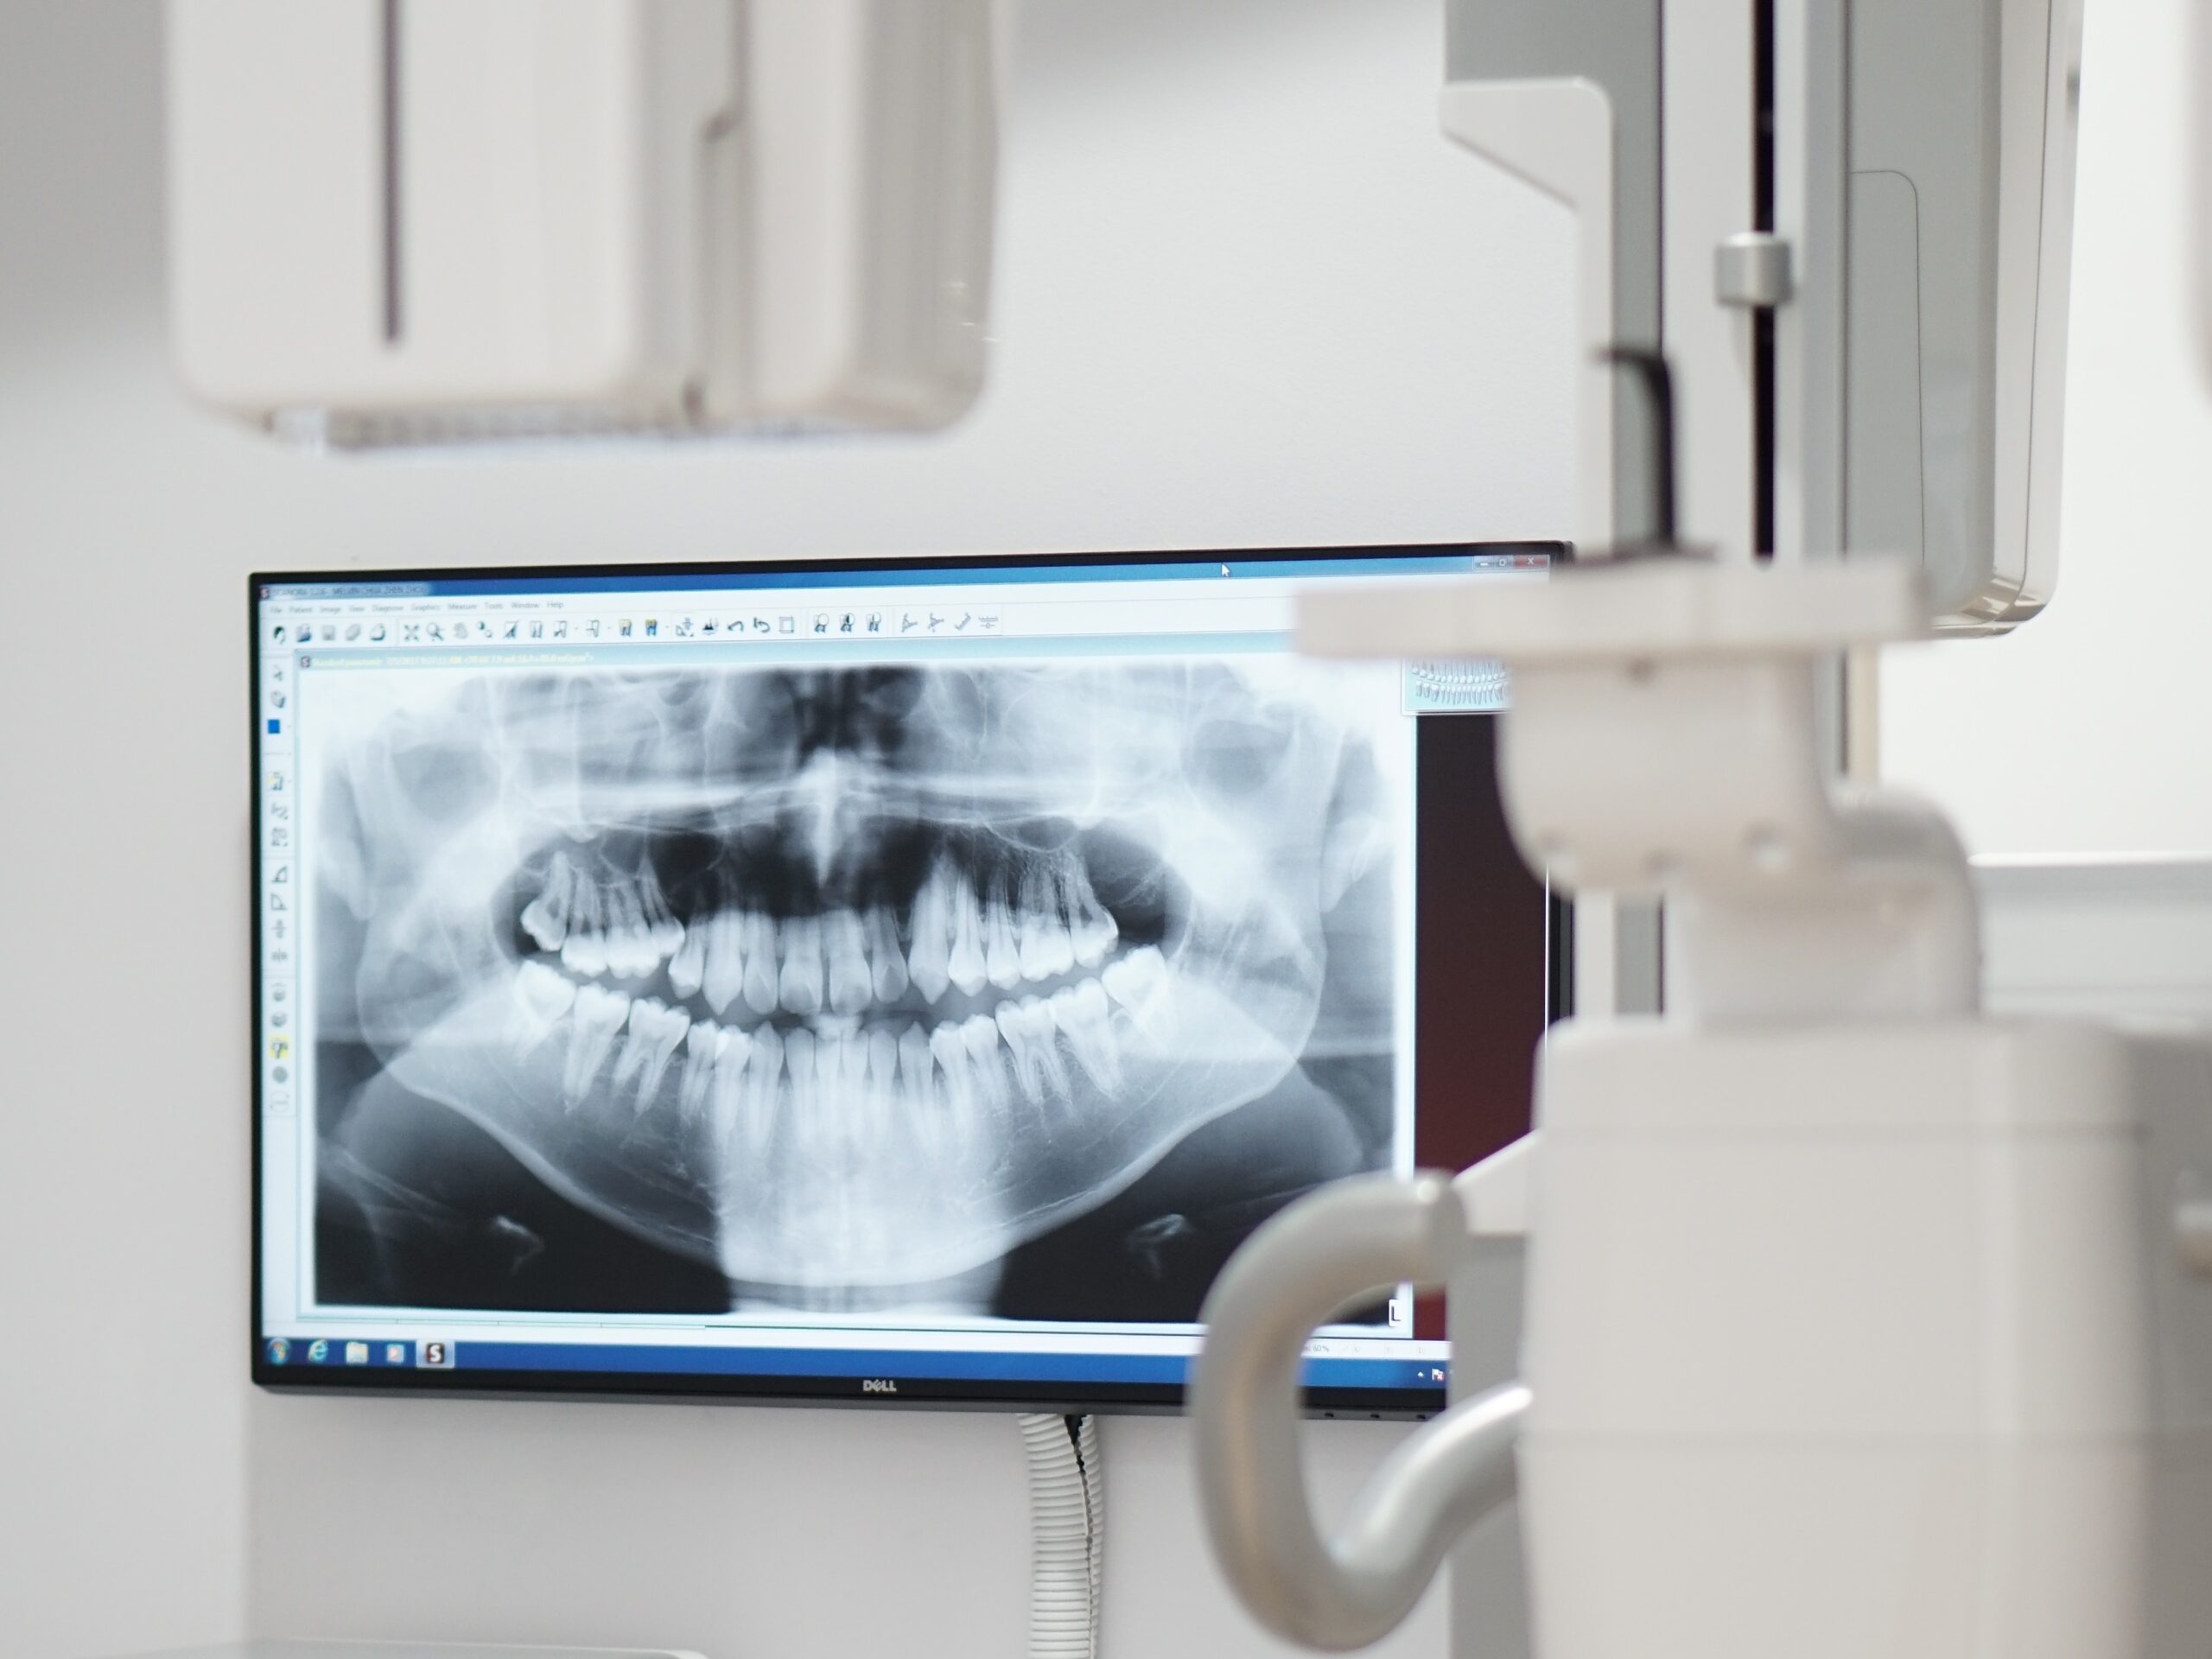

Dental X-Ray

Accurate dental imaging to reveal hidden oral issues before symptoms show.

Dental X-rays at Ocean Dental use advanced digital imaging to detect hidden oral problems that regular exams miss. They help identify tooth decay, bone loss, impacted teeth, and jaw abnormalities early. These scans support timely diagnosis and effective treatment planning. Safety and clarity are prioritized using low-radiation digital machines with lead-apron protection.

- Panoramic X-Ray (OPG) – Captures your full upper and lower jaw. Useful for wisdom teeth, jaw joint issues, and braces planning.